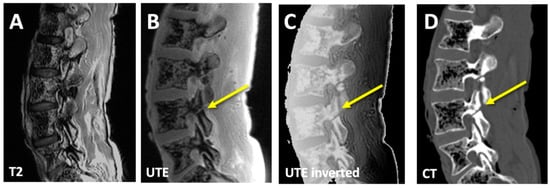

3.1. CT-like Images